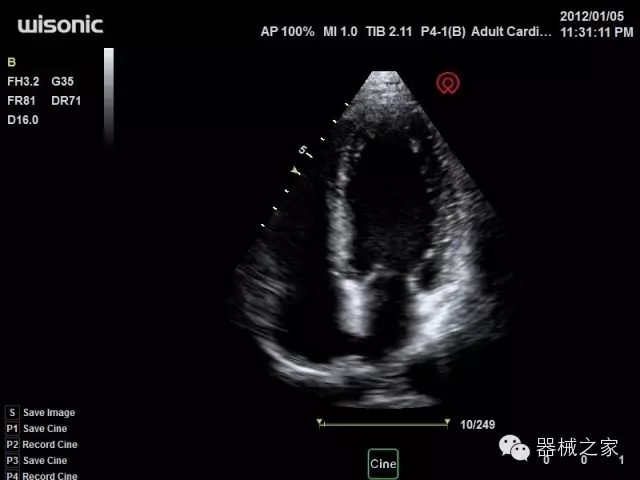

經(jīng)典產(chǎn)品:四葉草

臨床圖片賞析

產(chǎn)品特點(diǎn)

·全球目前唯一一款配備主機(jī)雙探頭接口,整機(jī)重量(含電池)在5公斤以內(nèi)的便攜式彩超;

·獨(dú)有的HoloTM PW 實(shí)時(shí)3取樣門PW成像技術(shù),精確進(jìn)行血管診斷;

·一鍵優(yōu)化B、Color、PW,Auto Doppler自動(dòng)識(shí)別血管位置、偏轉(zhuǎn)角度等,提高工作效率;

CFDA注冊證編號(hào)

·粵械注準(zhǔn)201522231208